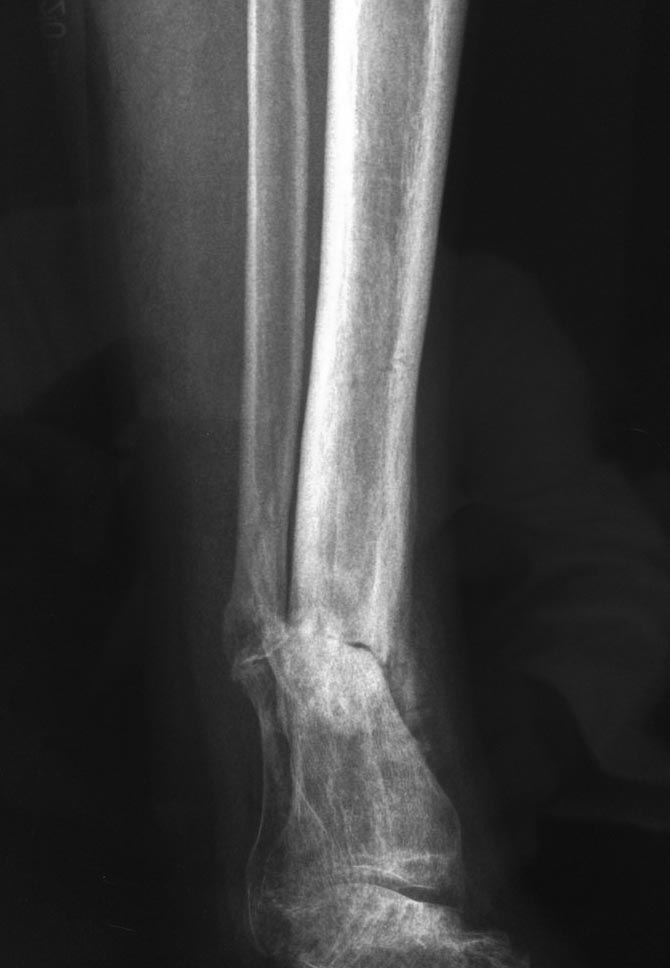

Уважаемые коллеги выразите Ваше мнение по следующему случаю. Молодой

человек, 27 лет, находится на лечении с диагнозом: Ложный сустав

большеберцовой кости в нижней трети, фиксированный интрамедуллярным

блокированным стержнем (12.02.2014 г), ложный сустав малоберцовой кости

в нижней трети левой голени, посттравматический артроз левого

голеностопного сустава 1 стадии. Укорочение левой нижней конечности на

1,0 см. Со слов пациента известно, что в детстве получил перелом

большеберцовой кости, лечился консервативно, перелом сросся с

деформацией. Травма в июле 2010 г. бытовая - упал на лестнице, получил

перелом малоберцовой кости, и перелом большеберцовой кости без смещения.

В январе 2014 г. установлен диагноз: Ложный сустав большеберцовой кости

в нижней трети, малоберцовой кости в нижней трети левой голени.

Контрактура сгибательно - разгибательная левого голеностопного сустава.

Посттравматический артроз левого голеностопного сустава 1 стадии.

Укорочение левой нижней конечности на 1,0 см.